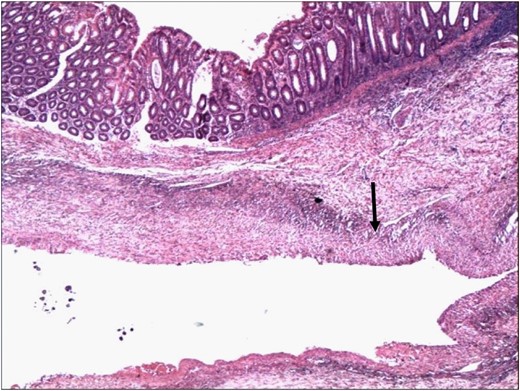

Histopathology confirmed the specimen to a SAA, with a 1 cm rupture through the colonic wall (Fig. 3A and B). On microscopic examination, the wall of the colon showed attenuation and loss of the muscle layers with bleeding into the lumen of the colon (Figs 4 and 5).

Point of rupture of the aneurysm into the lumen of the colon. The lumen of the aneurysm contains blood clot (arrowhead) (H&E 4×).